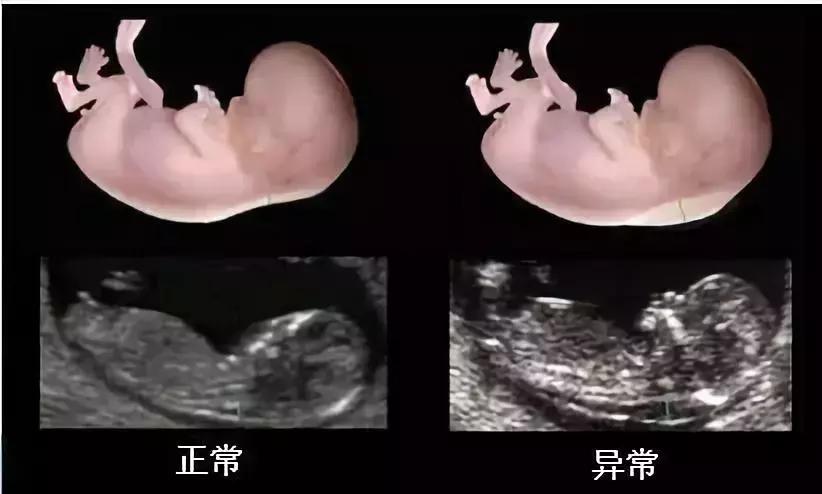

NT指的是“胎儿颈项透明层”,它反映了胎儿颈背部皮肤层与筋膜层之间淋巴液体聚积的厚度,可以称的上是一次畸形小筛查。颈项透明层越厚,胎儿发生异常的概率就越大。

正常NT数值:11周—13周+6天小于3mm,大部分是2.5mm,大于等于3mm发生胎儿异常的可能性增加。

NT增厚约10%合并胎儿染色体异常,最常见21三体综合征;NT越厚,染色体异常的风险越高;与胎儿畸形和不良妊娠结局密切相关,尤其先天性心脏病危险度为NT正常儿的6倍。